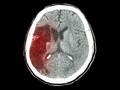

[ISC2015]ESCAPE:血管内治疗降低缺血性卒中患者死亡率

ESCAPE试验结果显示,快速血管内治疗可改善功能预后并使近端血管闭塞的缺血性卒中患者的死亡率减半。研究于2015年2月11日呈现在2015年国际卒中大会

2015-02-12